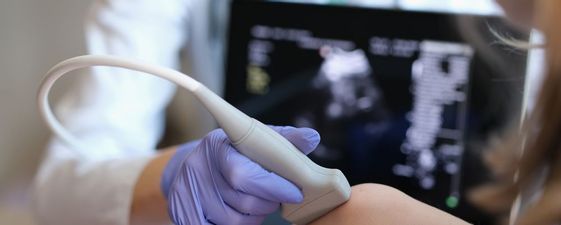

При проведении исследования специалист получает четкое изображение мягких тканей, а также сухожилий, мышц, связок, околосуставных сумок, гиалинового хряща и нервных стволов. Датчик с высокой точностью улавливает сигналы, преобразуя их в картинку на экране, что позволяет врачу в режиме реального времени анализировать состояние всех составляющих локтя и обнаруживать признаки возможных или уже имеющихся заболеваний.

Для обеспечения плотного контакта датчика с поверхностью кожи применяется прозрачный гипоаллергенный гель. Специалист перемещает плавно датчик в области изучаемого сустава, получая на экране четкую картину состояния анатомических структур. Изменяя положение сенсора, доктор изучает суставные ткани под разными углами, что позволяет обнаружить отклонения. В процессе осмотра выполняются необходимые замеры визуализируемых элементов.